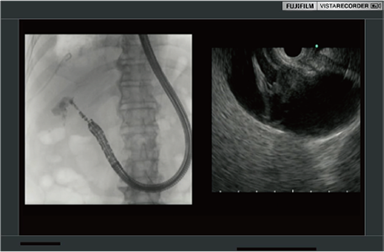

録画範囲のトリミングにより、内視鏡画像も透視画像も大きくPinP録画。特に内視鏡と透視を1:1で録画するときに役立ちます。

EUS